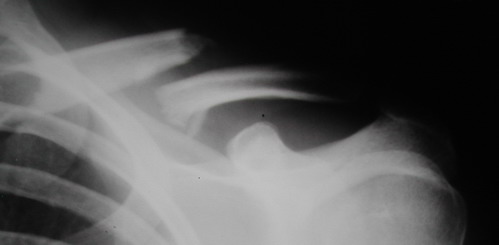

Во время стажировки в Австрии не мог не поинтересоавться, как австрийские хирурги лечат переломы ключицы. Оказалось, при переломах без смещения или с небольшим смещением накладывают восьмиобразную повязку, в остальных случаях выполняют остеосинтез пластинами.

Однако, чтобы уснуть с аппаратом внещней фиксации на ключице нужно "устать" не меньше, чем в рамке Чижина. К тому же, у некоторых больных присутсвует страх, что что-то в аппарате может раскрутиться, зацепиться за одеяло или подушку, или воспалиться. Крепко спят пациенты после качественного стабильного погружного остеосинтеза, когда ничего не торчит на коже. Особенно сладко спится после принятия душа или ванны. Это возможно после снятия швов. А вот у "чижиков" и "аппаратчиков" с полноценными водными процедурами определенные трудности.

Хотя с точки зрения кожных рубцов на видном месте, рамка Чижина и аппарат имеют явное преимущество. Но в ущерб "качеству сна"...